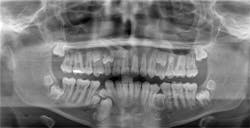

The presence of protrusive occlusion is noted in the extraoral examination. Upon taking a Panorex for the patient, you discover an increased number of teeth leading to a diagnosis of supernumerary teeth. It is suggested to the patient and parent that additional evaluation rule out other syndromes and disorders associated with multiple supernumerary teeth.

A prophylaxis and home-care instructions are completed at the appointment. The patient is asked to consider an appointment with an expert in a local hospital, but the mother declines the invitation. During the appointment, the mother indicates that both she and her mother have a history of multiple supernumerary teeth. Since there are a number of genetic disease states that are associated with multiple supernumerary teeth, the dentist further encourages a complete evaluation for such diseases. In this case, the number of supernumerary teeth is significant (see Figure 1). Specific considerations for this patient would be cleidocranial dysplasia (CCD) and Gardner syndrome.

When viewed radiographically, the indications are often very clear with numerous supernumerary teeth present. Patients routinely have 10 or more supernumerary teeth that are producing crowding and preventing eruption of deciduous teeth. There is an obvious mix of dentition with this disorder. Another characteristic of the disorder is the lack of deposition of cellular cementum on the roots of the teeth.